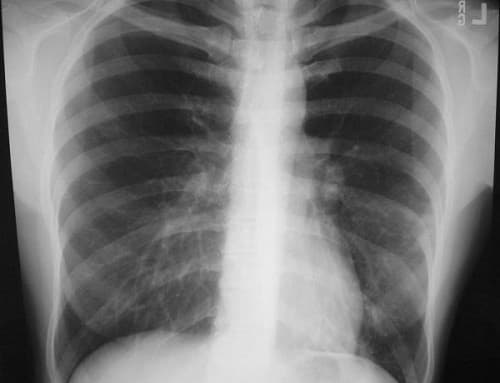

ung thư phổi